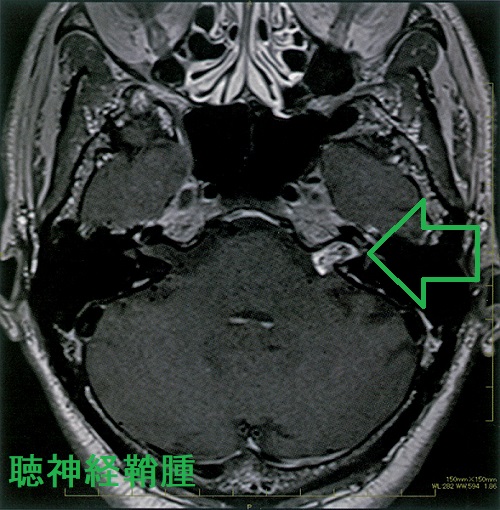

もっとも頻度が高い神経鞘腫(シュワノーマ)は聴神経腫瘍です。聴神経腫瘍の症状は

- 耳鳴・聴力低下(蝸牛神経障害)

- めまい、ふらつき(上前庭神経、下前庭神経障害)

- 顔面神経麻痺(顔面神経と聴神経は並走しているため)

などです。

これらの症状がある場合や、腫瘍が大きく脳を圧迫している場合は

- 手術摘出+残存腫瘍にサイバ-ナイフ、ガンマナイフの放射線治療

- 放射線治療のみ

聴神経は非常に脆いため、術後の麻痺を考えた上でどちらにするのか決めます。

また、術後顔面神経麻痺を来す場合もある。多くは一時的だが、永続性の場合は再建手術も。

聴神経鞘腫に次いで多いのが三叉神経鞘腫で、舌下神経鞘腫もある。